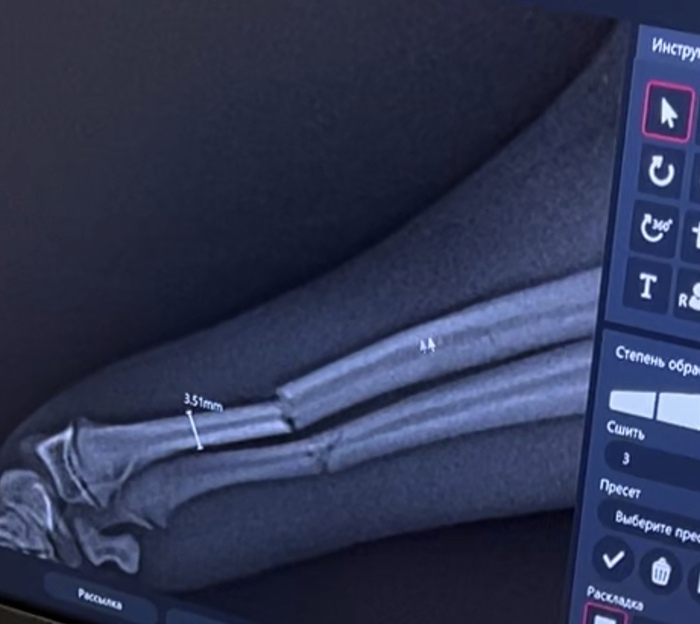

В ветеринарке, сразу после перелома

Перелом лучевой кости, размеры кости. Накладывали титановую пластину